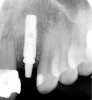

Figure 2  Identification of sufficient inter-radicular space: The radiographic representation of inter-radicular space (Fig 2) reveals abundant space for a single-tooth implant; at the alveolar crest, > 6 mm of interproximal space is available for placement of a 4-mm implant without encroaching on bone and periodontal ligament at the adjacent teeth. The 5-year-follow-up radiograph (Fig 3) reveals the interproximal maintenance of bone at this implant/abutment interface and adjacent teeth, in part due to proper planning and implant placement.

Figure 2

Figure 3  Identification of sufficient inter-radicular space: The radiographic representation of inter-radicular space (Fig 2) reveals abundant space for a single-tooth implant; at the alveolar crest, > 6 mm of interproximal space is available for placement of a 4-mm implant without encroaching on bone and periodontal ligament at the adjacent teeth. The 5-year-follow-up radiograph (Fig 3) reveals the interproximal maintenance of bone at this implant/abutment interface and adjacent teeth, in part due to proper planning and implant placement.

Figure 3